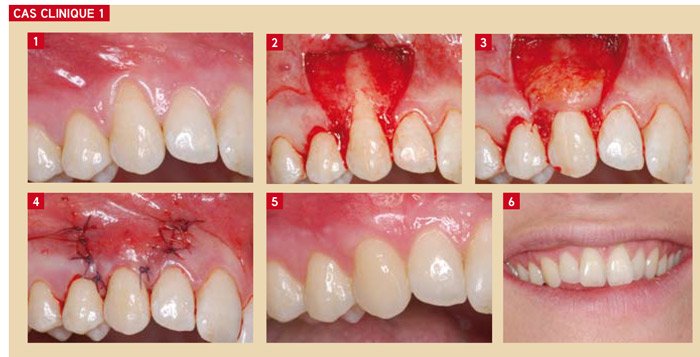

Cas Clinique n°1 : Récession unique en zone esthétique chez une jeune adulte

Présentation du patient : Femme de 28 ans, non fumeuse, en bonne santé générale. Consultation pour récession gingivale visible sur la canine supérieure gauche (23), associée à une hypersensibilité dentinaire au froid et à une gêne esthétique majeure. Hygiène bucco-dentaire correcte. Indice de plaque < 15 %.

Problématique identifiée : Récession de classe I de Miller de 3 mm de hauteur, avec tissu kératinisé insuffisant apicalement (1 mm). Sourire gingival modéré.

Prise en charge : Après thérapeutique initiale et réévaluation à 6 semaines, une greffe conjonctive avec recouvrement total du greffon (GC + LPC) est réalisée. Le greffon est prélevé au palais par technique de Bruno. Le lambeau positionné coronairement recouvre intégralement le greffon.

Résultat attendu : Recouvrement radiculaire complet, intégration chromatique excellente, disparition de l’hypersensibilité, épaississement gingival durable. Ce cas illustre parfaitement la supériorité esthétique de la greffe conjonctive enfouie en zone antérieure.